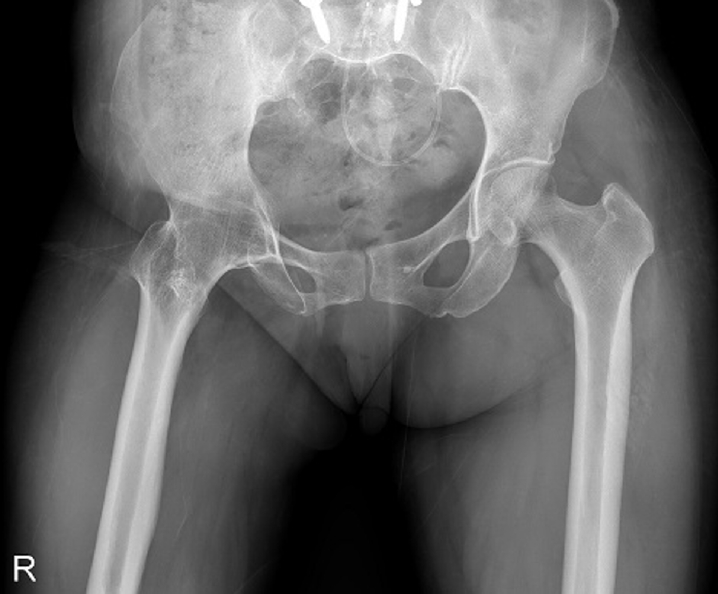

Fig. 2.

Radiograph obtained 3 years earlier of a 58-year-old female patient presenting with a right subtrochanteric femoral fracture (anteroposterior view).

Case 1: synostosis of hip joint

A 58-year-old female patient visited our emergency room, complaining of pain in the right hip that occurred the day before her hospital visit. She had a history of restricted right hip range of movement following a dislocation of the right hip in her youth, and she typically walked with a cane. The day prior to her visit, while lying on her right side and sleeping, she developed pain in the right hip area without any history of trauma. Upon examination, the patient had a background of hypertension and exhibited a bone mineral density (BMD) of ‒0.1 in the femoral neck. Notably, she had no history of malignancy. Initial physical examination and computed tomography scans conducted upon her arrival did not reveal any signs of malignancy or infection at the fracture site, indicating a low likelihood of these conditions as contributing factors. Radiographic evaluations, including both hip anteroposterior and right axial views, demonstrated signs of synostosis involving the right femoral head and acetabulum. A fracture was observed in the subtrochanteric area of the right femur, characterized by a beak-shaped thickened cortex on the lateral side of the fracture site. Importantly, the radiographs obtained 3 years prior showed no abnormalities at the fracture site (Figs. 2, 3). Following the diagnosis, the patient underwent open reduction and internal fixation using a plate. Subsequent follow-up indicated successful bone union at the fracture site.